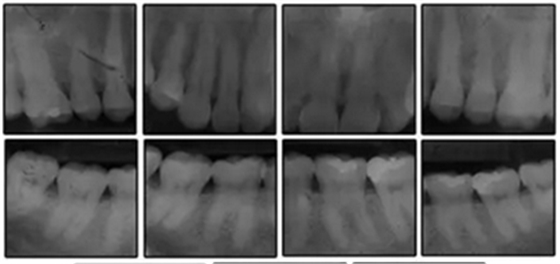

患者是一名39歲的白人婦女,病史不明。她主訴是她的右側(cè)顳下關(guān)節(jié)有不適癥狀,并希望改善她的笑容。她有一個(gè)對(duì)稱的臉型和一個(gè)II類2分類的微笑。她的側(cè)貌是凸的,90°的鼻唇角和骨性下頜骨發(fā)育不足??趦?nèi),上頜中線與面部重合,但下頜中線向右側(cè)偏移5mm;存在6mm的深覆蓋。她的兩側(cè)都是I類磨牙關(guān)系,左側(cè)是I類尖牙關(guān)系,右側(cè)是完全的II類尖牙關(guān)系。下頜右側(cè)第二前磨牙先天性缺失(圖1和圖2)。最初的全景片顯示了足夠的骨質(zhì)水平和全部的第三磨牙(圖3)。治療前的頭影測(cè)量片片和相應(yīng)的頭影測(cè)量圖(圖3)證實(shí)ANB為7°,Wits評(píng)估為6 mm的骨性II類錯(cuò)合(表)。上頜切牙相對(duì)與面部和顱底的位置很好。下頜切牙前傾。診斷為II類2分類錯(cuò)合畸形,伴有骨性下頜發(fā)育不足,右側(cè)顳下頜關(guān)節(jié)癥狀,下頜中線向右側(cè)偏移5mm,先天性右下第二前磨牙缺失。

圖3. 治療前頭影側(cè)位片,頭影測(cè)量描跡圖和全口X光片

患者決定采用非手術(shù)治療方法,側(cè)貌沒(méi)有任何預(yù)期的變化。治療后面部照片(圖5)顯示她改善的微笑和側(cè)貌,包括尖牙保護(hù)合。由于先天性第一前磨牙缺失,右磨牙關(guān)系為III類。治療后牙齒石膏模型(圖6)顯示實(shí)體牙齒交錯(cuò)排列情況,并且全景X線片顯示可接受的牙根平行度而且沒(méi)有牙根吸收表現(xiàn)(圖7)。最終的頭影測(cè)量片(圖7)證實(shí)了面部評(píng)估,并且描跡圖顯示深覆蓋的改善,同時(shí)保持上頜切牙位置并通過(guò)測(cè)量ANB角度和Wits評(píng)估改善骨性II級(jí)關(guān)系(表)。治療前后的疊加圖顯示由于下頜切牙前傾的增加改善了下唇平衡(圖8)。如相關(guān)治療計(jì)劃所預(yù)測(cè)的那樣,B點(diǎn)出現(xiàn)。A進(jìn)行牙科錐形束計(jì)算機(jī)斷層掃描以記錄下頜前牙區(qū)的骨質(zhì)變化。如預(yù)期的那樣,由于治療導(dǎo)致該區(qū)域的骨量增加(圖9)。